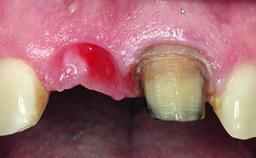

Replacement of a Missing Upper Left Central Incisor: Late Placement of an RC Bone Level Implant, CAD/CAM Zirconia Abutment

A healthy 37-year-old female patient was referred for a consultation on the replacement of missing tooth 21 with an implant-supported restoration. She stated that several years previously the tooth had been traumatically avulsed following a motor vehicle accident. The tooth was replaced with a three-unit fixed partial denture (FPD) immediately afterwards. Over time, she became disillusioned with the FPD and looked for a different option, including orthodontic therapy. She presented still in her orthodontic appliances, with the pontic sectioned free from the FPD but attached to the archwire. Her orthodontist felt that orthodontic treatment had been successfully completed, but nevertheless referred her before removing the appliances in case adjustments were necessary.